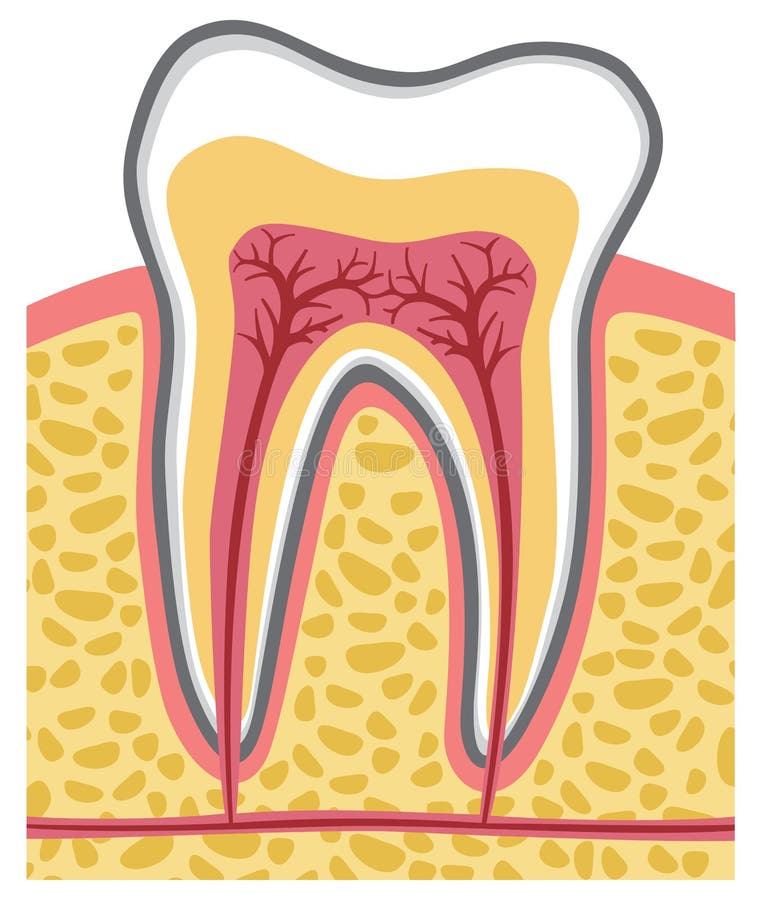

Tanden strukturerar Medicinskt diagram av strukturen av det inre tvärsnittet av tanden